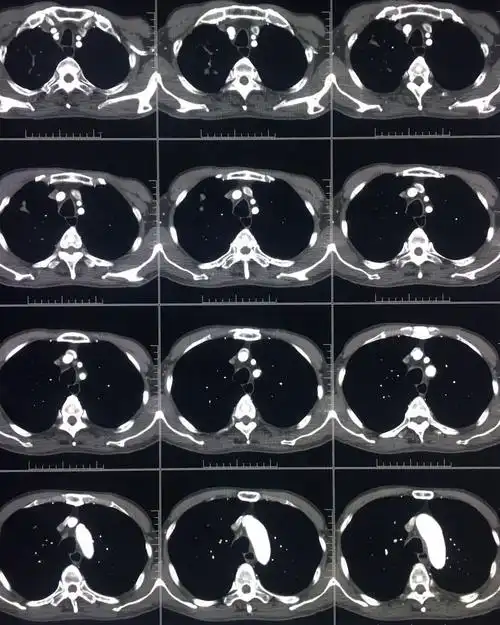

胸部ct平扫图片金典

外院ct平扫

ct平扫 三期增强,这个纵隔占位有点难 [病例帖]